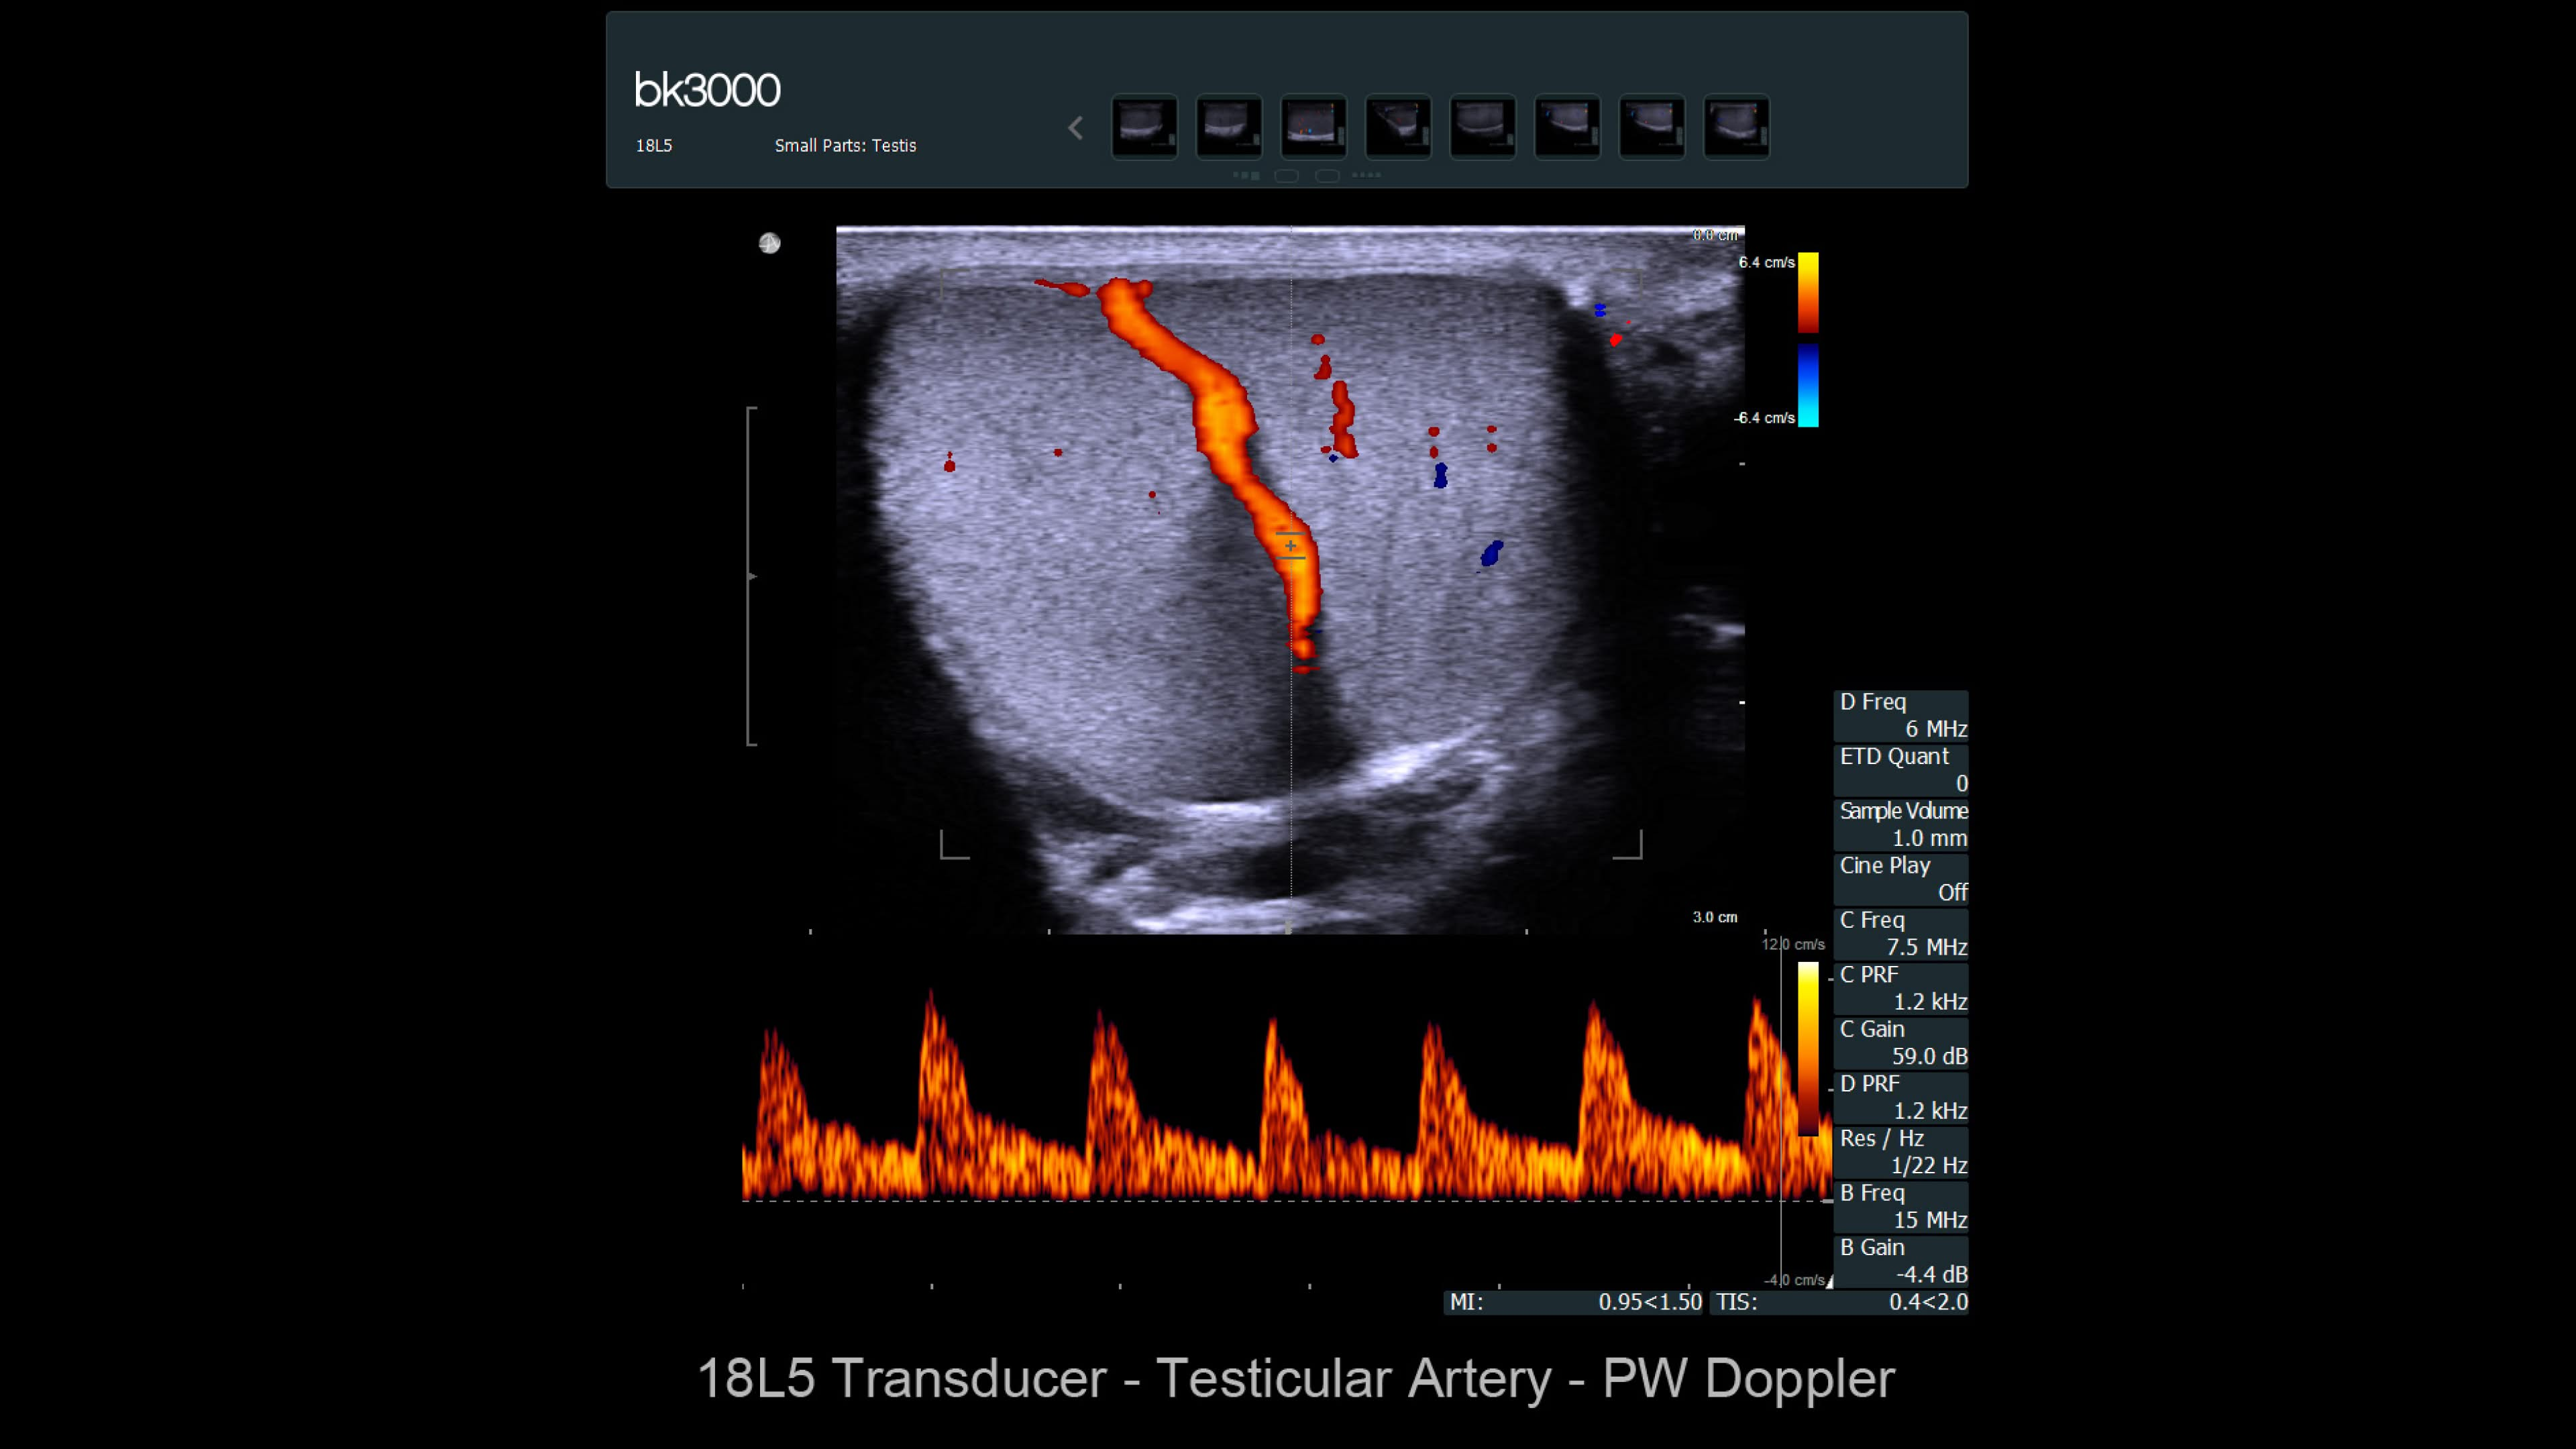

Ultrasound provides detailed information for kidney imaging, measurement, and biopsies. The bk3000 and bkSpecto systems help visualize fine anatomical details, see vascularization, measure blood flow, and locate kidney stones. The bkActiv, our flagship system, offers next-level imaging for prostate, renal, kidney, and bladder imaging, with sensitive Doppler for blood flow. Combined with sterilizable transducers, the bkActiv sets a new standard for surgical urology.